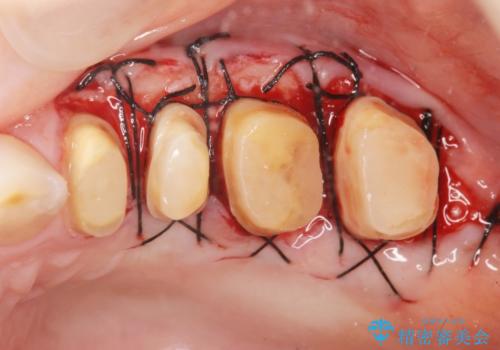

虫歯の深化により根管治療、歯周外科手術を行い歯肉の状態を改善し精密なセラミッククラウンを製作する治療を計画します。

セラミック治療の長期的な予後を見込むために、根管治療、歯周外科を行いクラウン装着前の環境を整えておくことが肝要です。